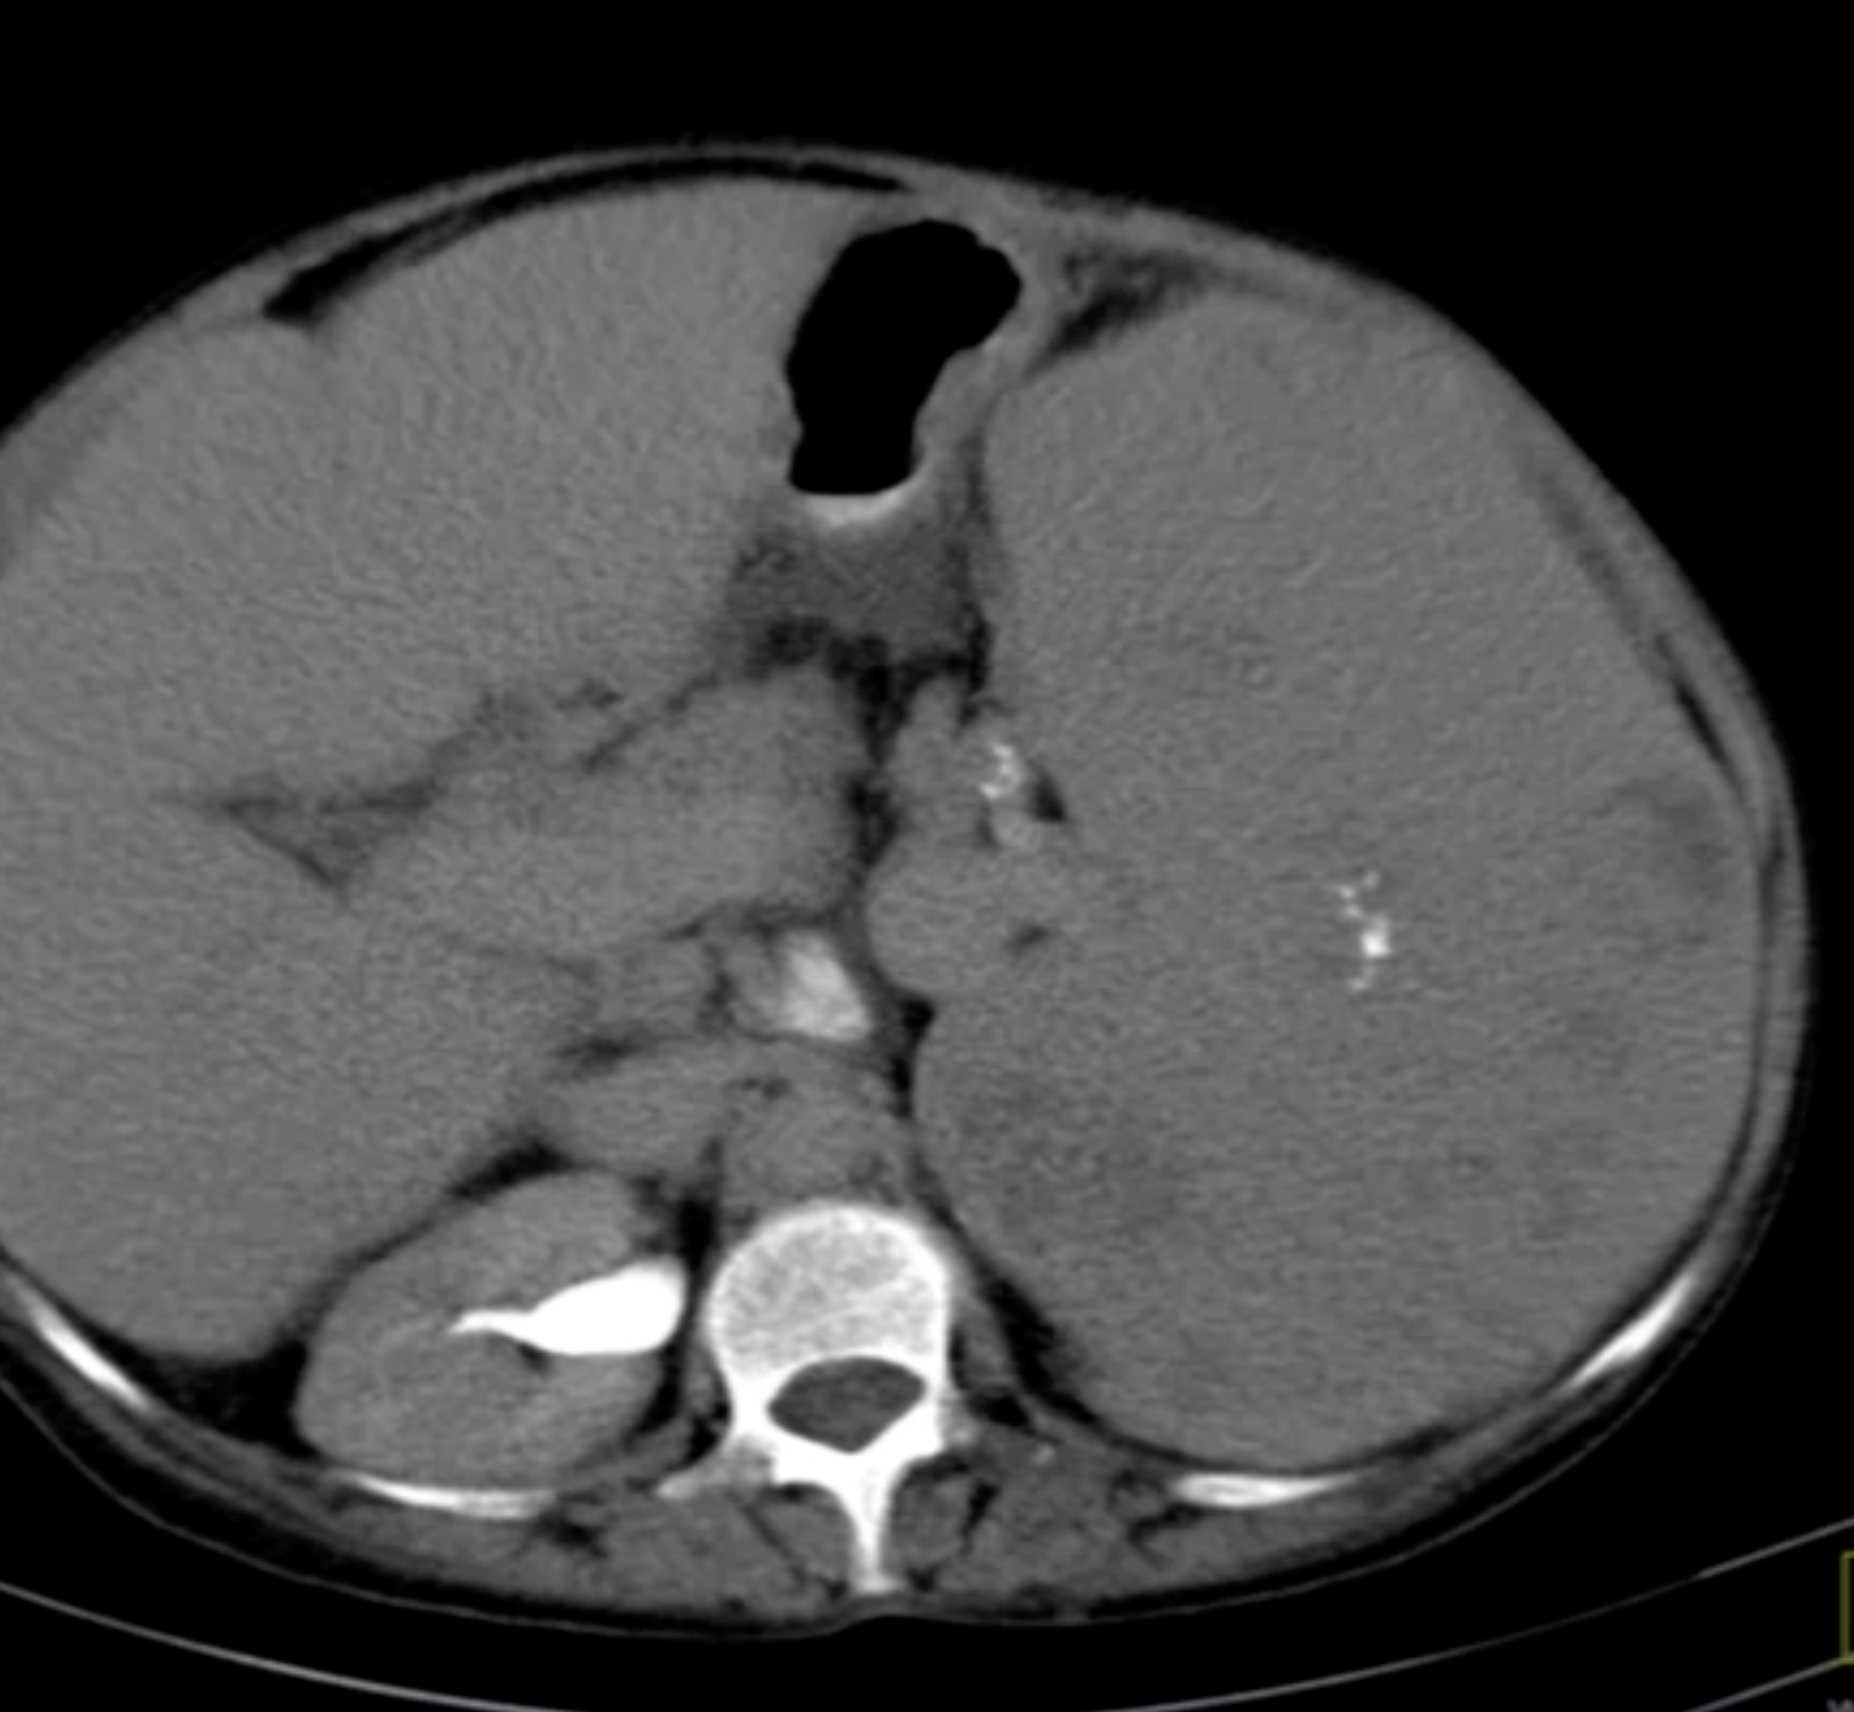

Gaucher's Spleen